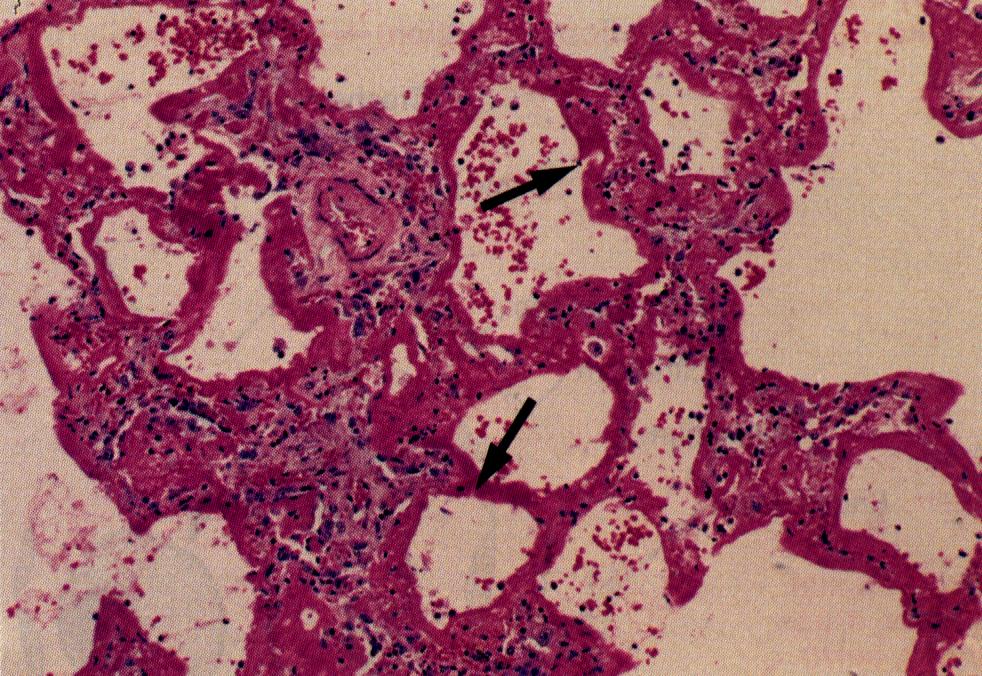

Las características macroscópicas de los pulmones con congestión y edema son el aumento de peso y la presencia de líquido, fundamentalmente en los lóbulos basales. Este fenómeno se observa en las imágenes radiológicas y en casos extremos se traduce en derrame pleural. A nivel histológico hay congestión capilar y aumento de líquido en el intersticio En forma casi paralela existe también, en los espacios alveolares líquido libre y proteínas, las cuales se pueden teñir con eosina, dándole un color rosado al transudado intraalveolar (x). Al mismo tiempo se puede observa macrófagos cargados con hemosiderina en los capilares pulmonares como en el espacio intraalveolar. Estás células se denominan células cardiacas ya que el ejemplo más característico de esta patología es la Insuficiencia Cardiaca por Estenosis Mitral.

Este tipo de cardiopatía se caracteriza por un marcado aumento de la presión intraauricular izquierda producto de la estenosis, electtrocardiográficamente hay evidencias de hipertrofia auricular izquierda y el pulmón es el reservorio de la volemia acumulada en la aurícula izquierda. En la larga evolución natural de esta enfermedad se observa además de los cambios descritos secuelas como engrosamiento de los tabiques intra-alveolares producto de la fibrosis a consecuencia de microruptura de capilares por la severa congestión. Es importante mencionar de que a pesar de los cambios experimentados en esta patología, la pared endotelial se mantiene intacta en sus mecanismos de permeabilidad y los fenómenos descritos son una situación límite de las leyes de Starling, es decir aumento exagerado de la presión hidrostática del capilar pulmonar.